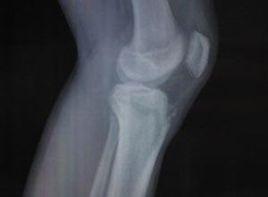

當肘關節伸直位摔倒時手部撐地,上肢處於外展位,外翻應力使肘關節外翻,同時前臂屈肌群猛然收縮,將內上髁撕脫,內上髁是一個閉合比較晚的骨骺,在未閉合以前骺線本身就是潛在的弱點。故可使發生骨骺分離,牽拉向下向前,並鏇轉移位。同時肘關節內側間隙暫時被拉開,或發生肘關節後外側脫位,撕脫的內上髁(骨骺),被夾在關節內,根據損傷的嚴重程度,可分為4度。

Ⅰdeg;損傷:僅有骨折或骨骺分離,移位甚微。

Ⅱdeg;損傷:骨塊向下有移位,並向前鏇轉移位,可達關節水平。

Ⅲdeg;損傷:骨折塊嵌夾在關節內,並有肘關節半脫位。

Ⅳdeg;損傷:肘關節後脫位或後外側脫位,骨塊夾在關節內。

兒童比成年人多見。受傷後肘內側和內上踝周圍軟組織腫脹,或有較大血腫形成。臨床檢查肘關節的等腰三角形關係存在。疼痛,特別是肘內側局部腫脹、壓痛、正常內上髁的輪廓消失。肘關節活動受限,前臂鏇前、屈腕、屈指無力。合併肘關節脫位者,肘關節外形明顯改變,功能障礙也更為明顯,常合併有尺神經損傷症狀。

發生肱骨內上髁的撕脫骨折時,肘關節內側組織,如側副韌帶、關節囊、內上髁和尺神經等均可損傷。肘關節內側腫脹,疼痛,局部皮下可見淤血。壓痛局限於肘內側。有時可觸及骨摩擦感。肘關節伸屈和鏇轉功能受限。

本病根據其外傷病史、臨床表現和X線檢查,一般能夠做出診斷,但對於一些特殊的情況,則仍然需要仔細的鑑別。尤其是要與肱骨內上髁骨骺相鑑別,肱骨內上髁骨骺約在6~10歲時出現,18歲左右閉合,但有時可能有不閉合者,應注意與骨折鑑別。